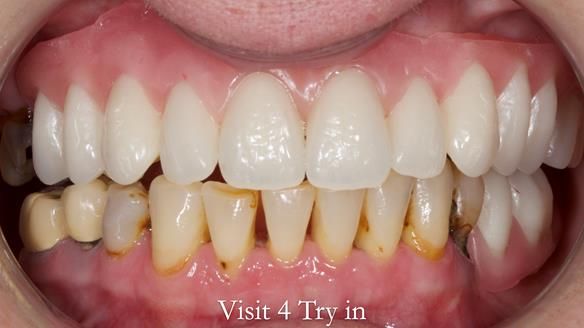

This newsletter describes the full protocol workflow of a complete upper denture and a lower partial denture for Jo.

The clinical situation and treatment process is shown in detail below. I provided the clinical work. Rowan Garstang provided the technical work. This treatment took 25 visits over a period of 12 months.